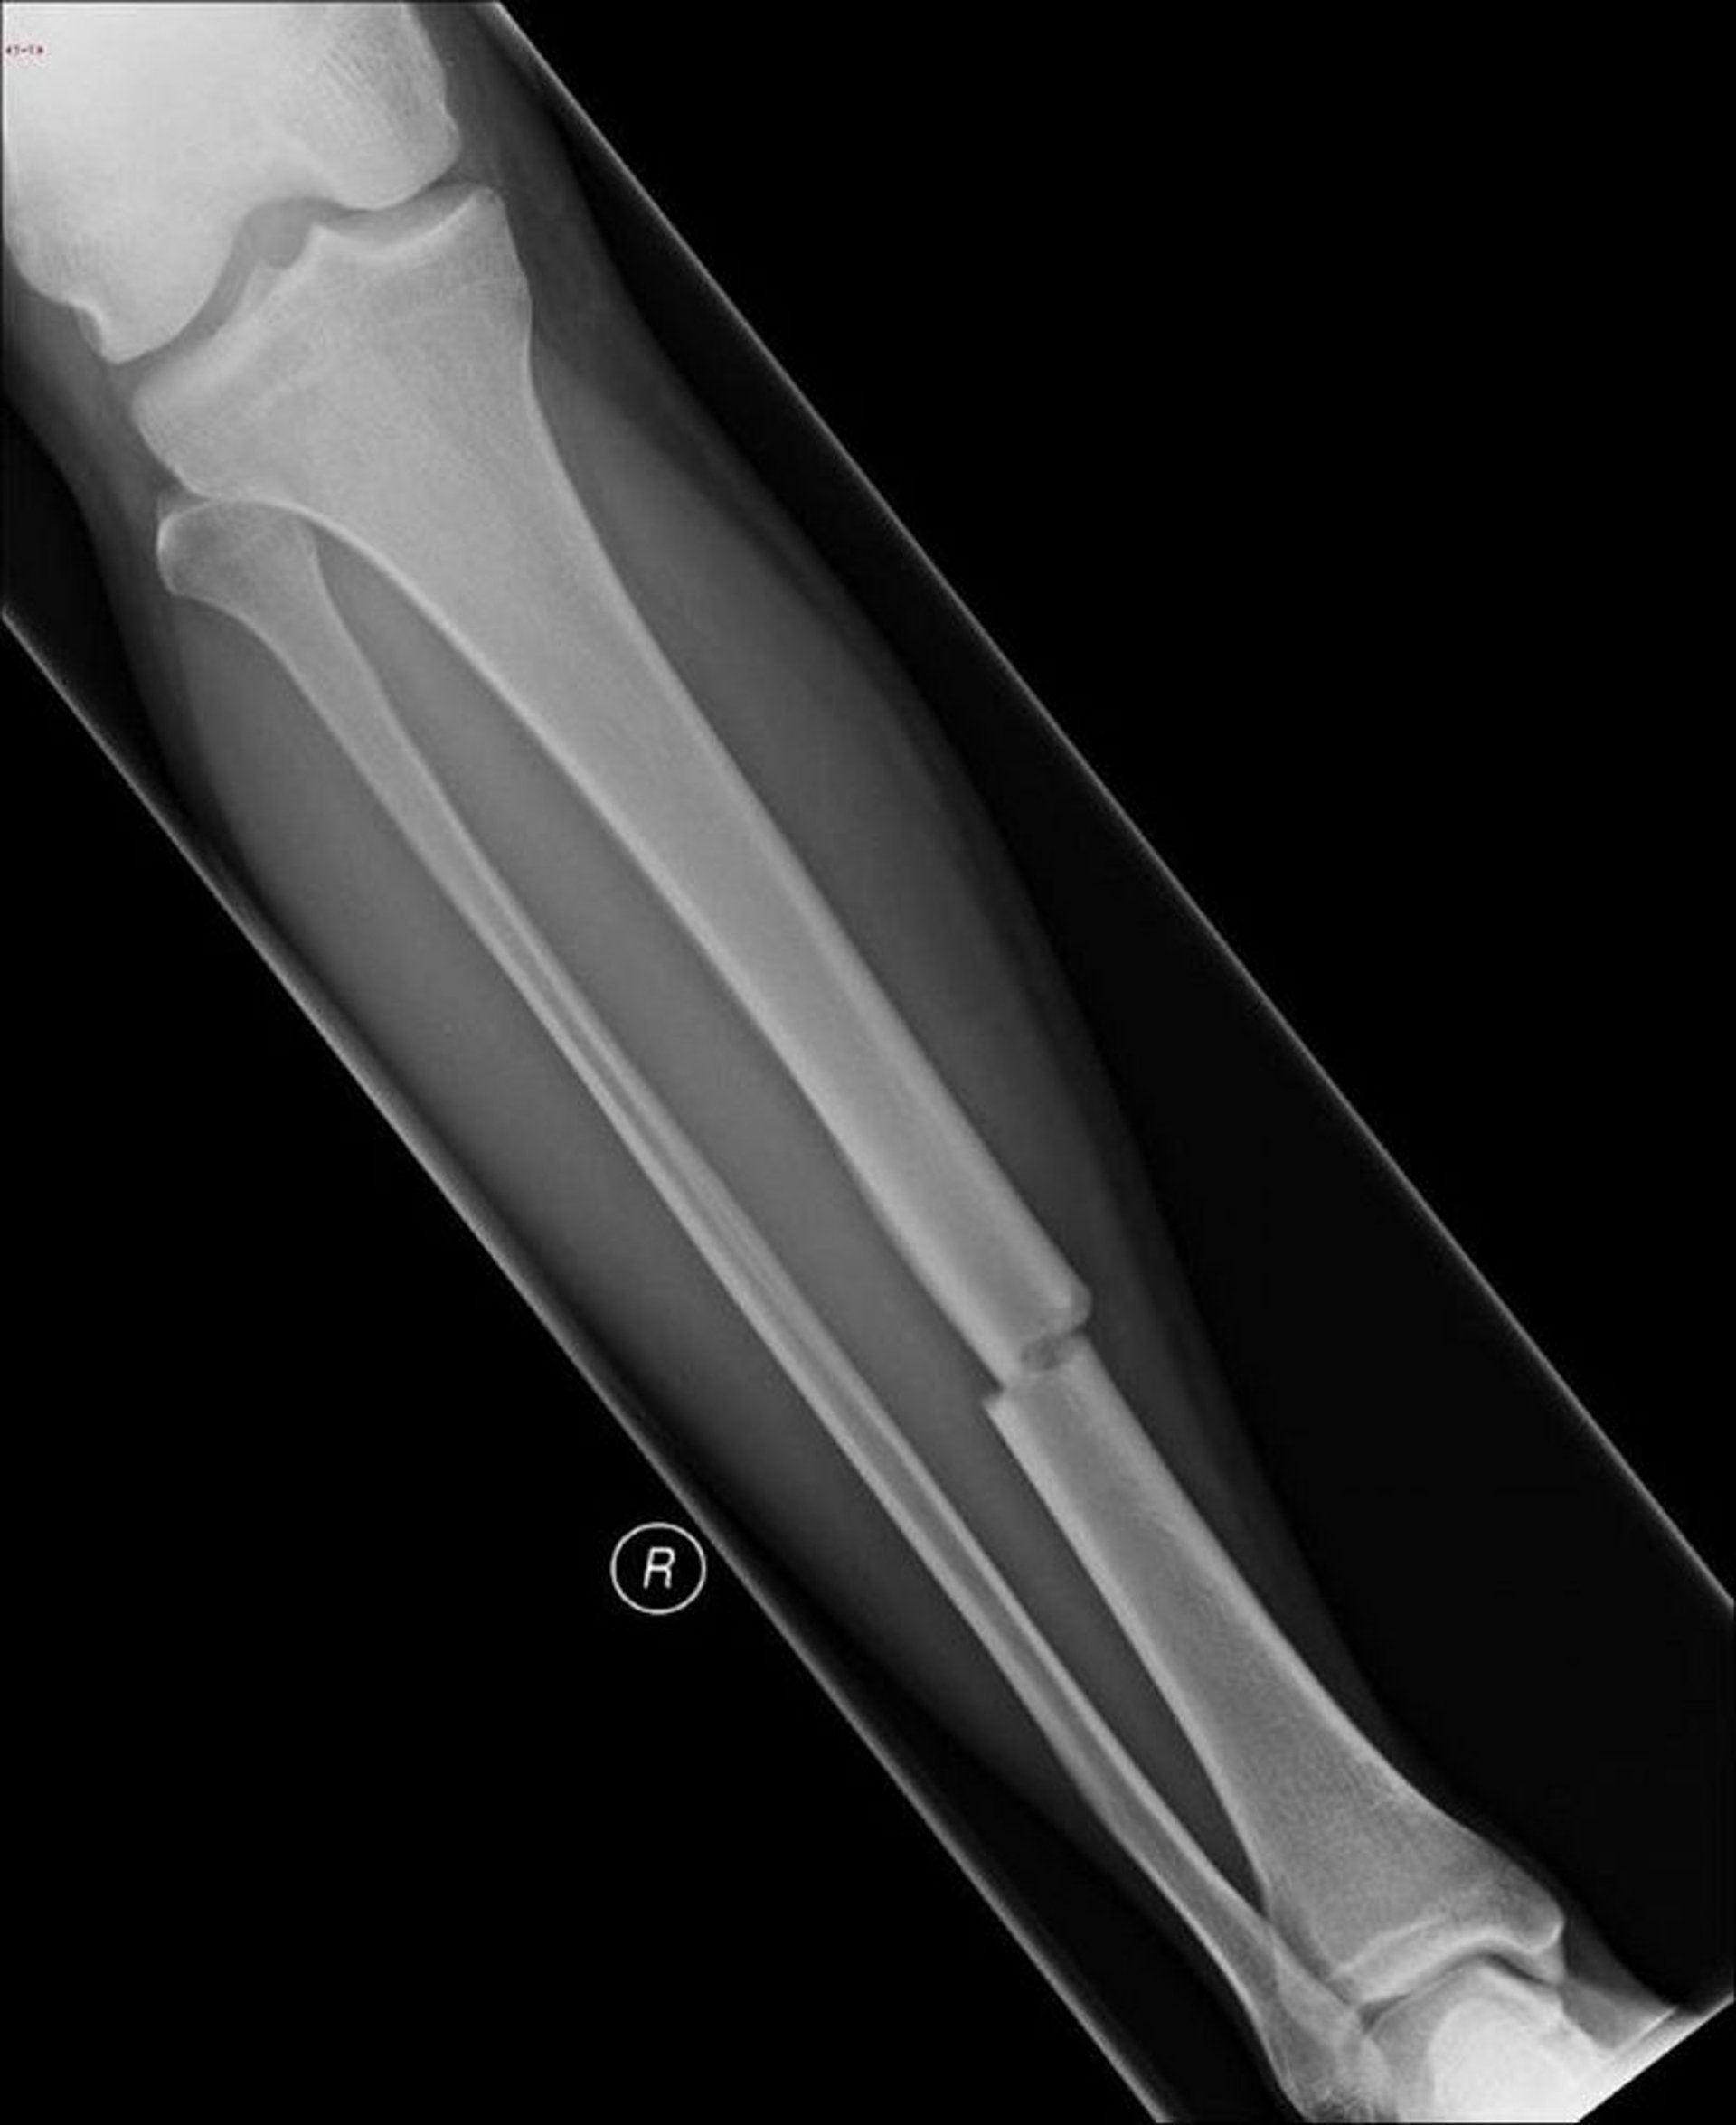

Fracture transversale de la diaphyse tibiale

Cette fracture transversale affecte le milieu de la diaphyse du tibia.

Image courtoisie de Danielle Campagne, MD.